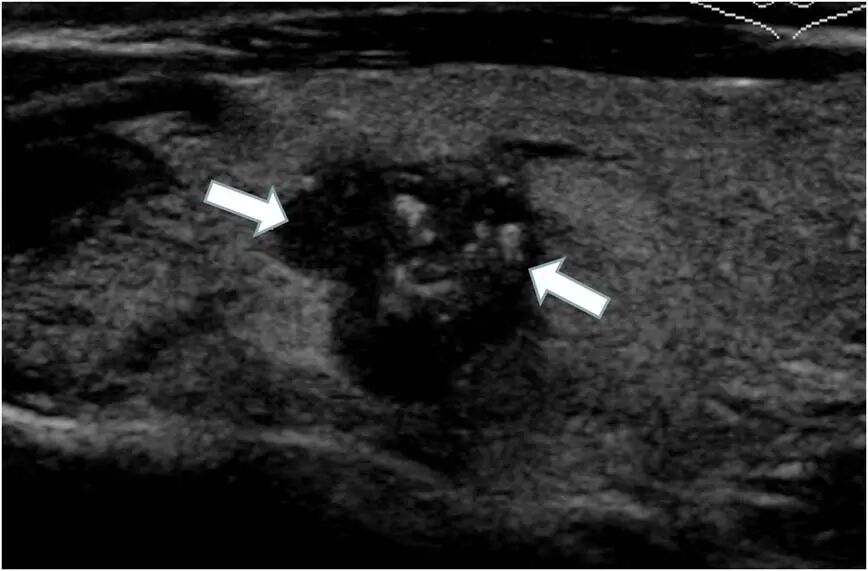

1.甲狀腺彩超和甲狀腺功能 :分別從結(jié)構(gòu)和功能兩方面檢查甲狀腺疾病。甲狀腺彩超不僅操作簡(jiǎn)單方便,還是無(wú)創(chuàng)的,是甲狀腺最常用且首選的影像學(xué)檢查方法。